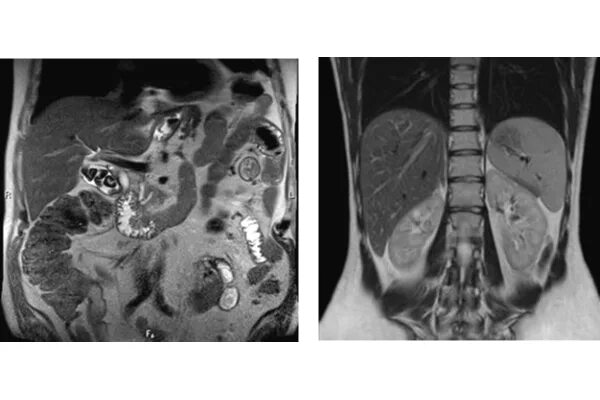

Камни в желчном мрт